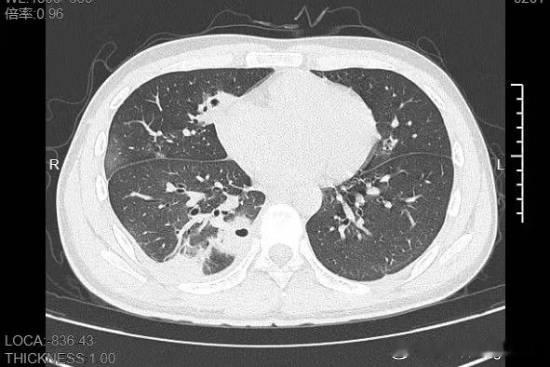

20岁男生肺被“啃”出10多个空洞 20岁男生挤颗痘痘,肺被“啃”出10多个空洞,这事儿一上热搜就把网友吓得不轻。大二学生小林,备考熬夜后脸上冒了颗黄豆大痘痘,没洗手就给挤了,当时还觉得清爽。结果没几天,痘痘化脓,他开始发烧咳嗽、胸部剧痛,体温烧到39℃,去医院一查,肺里十几个空洞,部分肺组织坏死,是血源性肺脓肿。原来,他血液里检出了藏在皮肤表面的金黄色葡萄球菌,祸根就是那颗被挤的痘痘。这也给爱挤痘的年轻人提了个醒,千万别手欠,挤痘有风险,下手需谨慎啊!